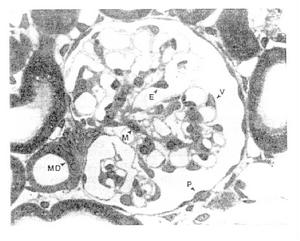

(2)小管毒性病變:環孢素的小管毒性病變是指短期環孢素治療引起的小管損害,與長期套用環孢素引起的環孢素慢性腎病屬於不同的概念。在環孢素治療的同種腎移植患者常規或細針活檢均能見到小管細胞的幾種形態學改變,包括巨大線粒體、小管細胞空泡形成和微鈣化等特徵性變化,但這些病變非環孢素毒性所特有。環孢素小管毒性的臨床表現與功能性腎毒性相似,但小球濾過率下降更顯著,奇怪的是無近端小管功能損害的表現,尿中溶酶體、N-乙醯葡萄糖苷酶排泄在正常範圍,無范科尼綜合徵報導小管毒性的出現是環孢素總體毒性的一種表現,因此可引導臨床醫師調整環孢素劑量,或停用與環孢素同時套用的其他腎毒性藥物。

在臨床實踐中,十分重要的是早期鑑別診斷急性環孢素毒性和急性排斥反應,但有時比較困難。臨床上,急性排斥反應常有尿量減少、發熱,超聲檢查顯示移植腎水腫,發生急性排斥反應的患者血肌酐增加比環孢素毒性反應迅速。尿鈉排泄減少和尿蛋白排泄增加在急性排斥反應雖少見,但高度提示排斥反應腎活檢顯示急性排斥時有瀰漫性細胞浸潤,而環孢素毒性反應有時伴有小動脈病變但是在無排斥反應的、接受環孢素治療的患者,炎症浸潤並不少見。另一方面,巨大線粒體、小管細胞空泡形成和微鈣化也可見於發生排斥反應的患者。

(3)環孢素慢性腎病(CsA-associated chronic nephropathy):長期環孢素治療最棘手的併發症是腎功能慢性進行性衰退,環孢素的這種腎損害被稱為環孢素慢性腎病,其病因是環孢素的慢性小管間質毒性(chronic tubulo-interstitial toxicity),其病理和臨床表現與慢性排斥反應難於區別代表環孢素慢性腎病最主要的特徵性病理改變是小動脈(arteriole)病變和間質纖維化而慢性排斥反應的三項主要病理改變為腎內較大動脈(artery)的內膜增厚間質浸潤和纖維化、腎小球硬化。環孢素慢性腎病的血管病變主要發生在小動脈(arteriole),包括小葉間動脈和弓形動脈。最近有報導環孢素慢性腎病可累及大動脈。環孢素引起的小動脈病(arteriolopathy)以兩種形式發生,其一為循環蛋白在小動脈壁沉積導致血管腔狹窄或阻塞,其二是內膜增厚,引起血管腔狹窄。這些病變進一步引起瘢痕化,繼發血管收縮和缺血導致小管塌陷和間質纖維化。在腎皮質可見不規則的灶狀或帶狀間質纖維化和小管萎縮病變

(1)環孢素慢性腎病的血管病變主要發生在小動脈(arteriole)包括小葉間動脈和弓形動脈最近有報導環孢素慢性腎病可累及大動脈。環孢素引起的小動脈病(arteriolopathy)以兩種形式發生,其一為循環蛋白在小動脈壁沉積導致血管腔狹窄或阻塞,其二是內膜增厚,引起血管腔狹窄。這些病變進一步引起瘢痕化,繼發血管收縮和缺血導致小管塌陷和間質纖維化在腎皮質可見不規則的灶狀或帶狀間質纖維化和小管萎縮病變。